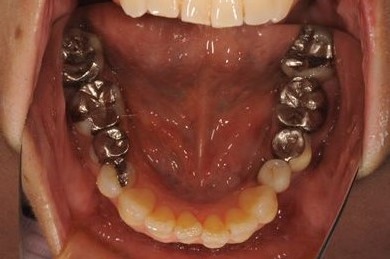

| 性別/年齢 | 女性 / 54歳 | ||||||||||||||||||||||||||||||||

| 主訴 | 下顎の奥歯を抜歯したままになっており、歯茎が少しやせて、両側の歯が少し倒れているような気がする。可能であればインプラントを入れたい。 | ||||||||||||||||||||||||||||||||

| 治療内容 | インプラント1本、メタルボンドセラミック1本 | ||||||||||||||||||||||||||||||||

| 総治療費 | 445,238円 | ||||||||||||||||||||||||||||||||

| 治療期間 | 5ヶ月 |